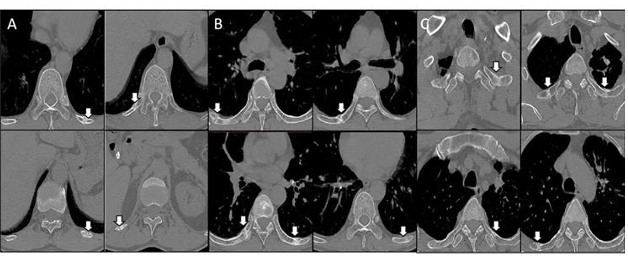

Thoracoscopic Neuroprotective Phrenotomy; A New Surgical Technique for Idio- pathic Incurable Chronic Hiccups